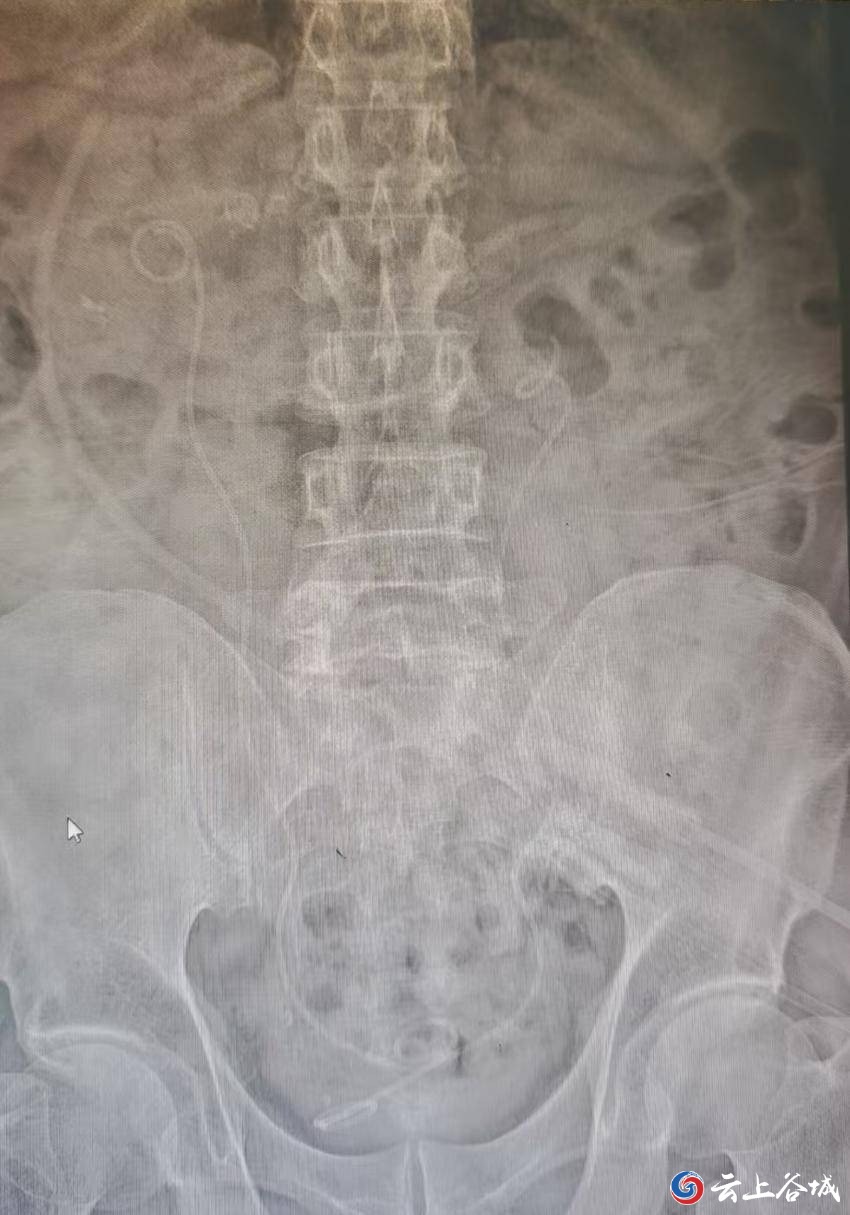

术后平片 “没想到麻醉效果这么好,手术中也没有不适,术后很快就能吃饭、下床,恢复得特别快!”王大爷术后感慨道。 谷城县人民医院在多学科协作下对高龄、危重患者实施个体化精准治疗,让“不可能”变“可能”,加速患者康复。 通讯员:何继海、颜鹏、郑晖 编辑:邓植元|审核:陈声权 琚晓青